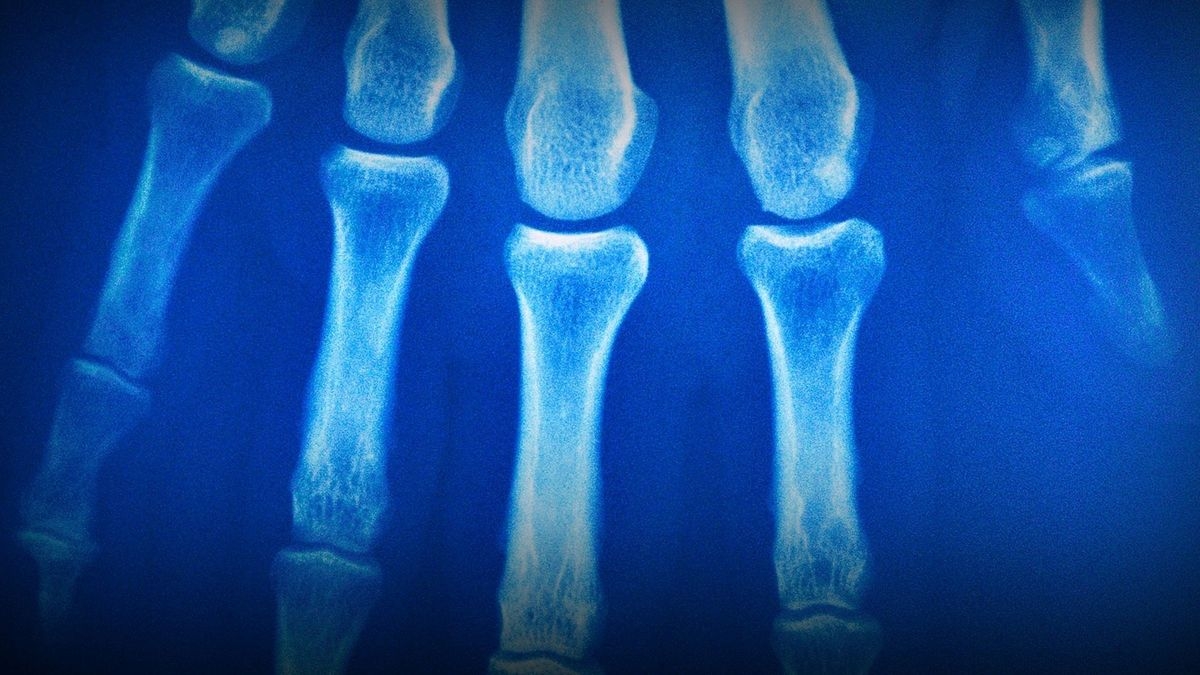

The stories of people who suffer from strange, life-altering illnesses are told on "Diagnose Me." Each of eight hourlong episodes documents two true stories of individuals whose health is being destroyed by the onset of symptoms that leave medical experts baffled. As the mysteries unfold, desperation turns to relief when doctors eventually uncover clues that lead to diagnoses and treatments. Featuring re-enactments bolstered by first-person accounts from patients, primary caregivers and doctors, the series celebrates medical professionals willing to try new protocols when encountering stranger-than-fiction cases.